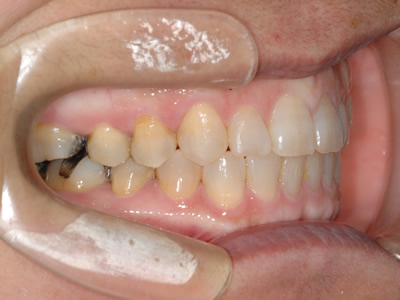

上顎前歯のガタガタと前歯の反対咬合を気にして来院されました。上下顎の左右第一小臼歯 (4番目の歯) を抜歯し、マルチブラケット装置で治療しました。治療期間は2年10ヶ月かかりました。

初診時